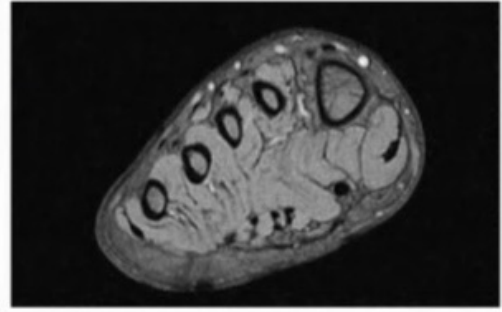

What kind of exam is this?

a. Wrist

b. Ankle

C. foot

What is the anatomical plain for the image above?

a. Axial

b. Sagittal

c. coronal

Key for 23-24 A medial meniscus B. lateral meniscus C. Tibia D. Fibula